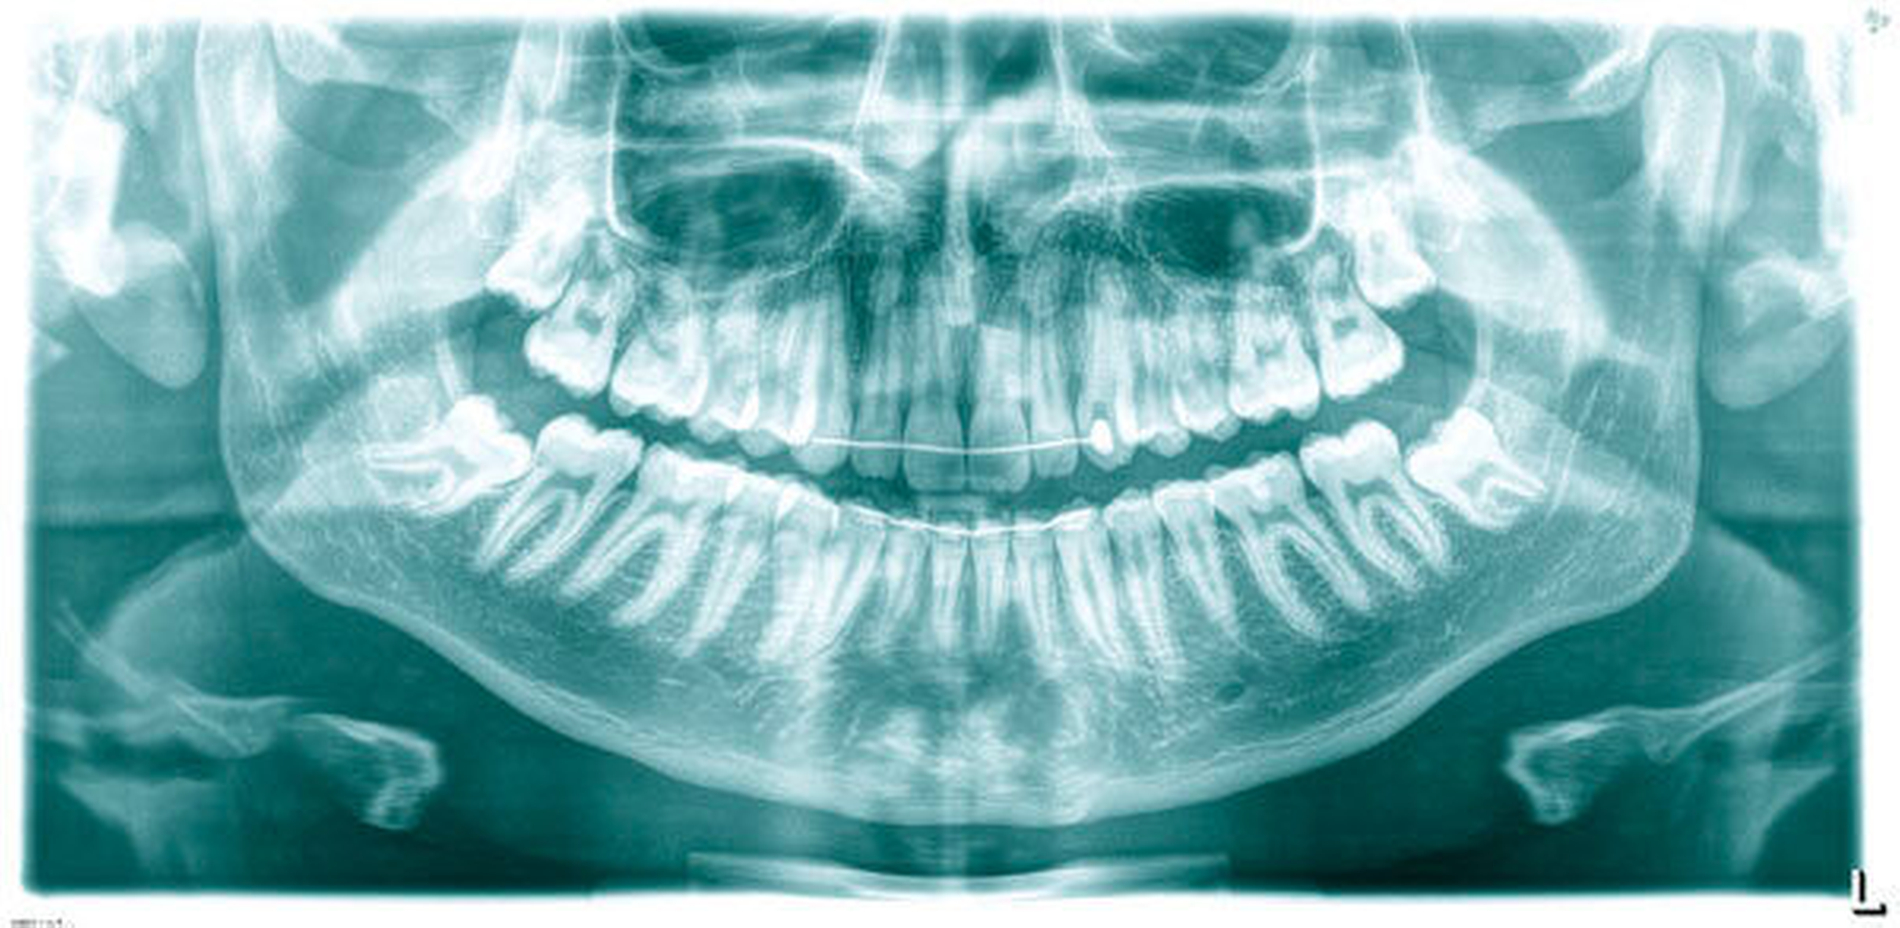

Der 17-jährige Patient stellte sich mit nicht auffindbarem Wurzelkanal Zahn 23 vor. Er war allgemeinanamnestisch unauffällig. Zum Zeitpunkt der Überweisung war die Trepanation bereits erfolgt und der Zahn provisorisch gefüllt. Ein präoperatives Röntgenbild, auf dem keinerlei Kanalstrukturen erkennbar waren (Abbildung 1) sowie ein OPTG (Abbildung 2) lagen vor. Der Patient klagte über spontanen Schmerz, der Zahn war perkussionsempfindlich, reagierte nicht auf den Kältetest. Der Klopfschall war unauffällig, der vestibuläre Knochen im apikalen Bereich druckschmerzhaft. Die Diagnose lautete symptomatische apikale Parodontitis.

Aus der zahnärztlichen Anamnese ging hervor, dass der impaktierte Zahn 23 mittels chirurgisch-kieferorthopädischer Extrusion vor drei Jahren in die Zahnreihe eingegliedert wurde.